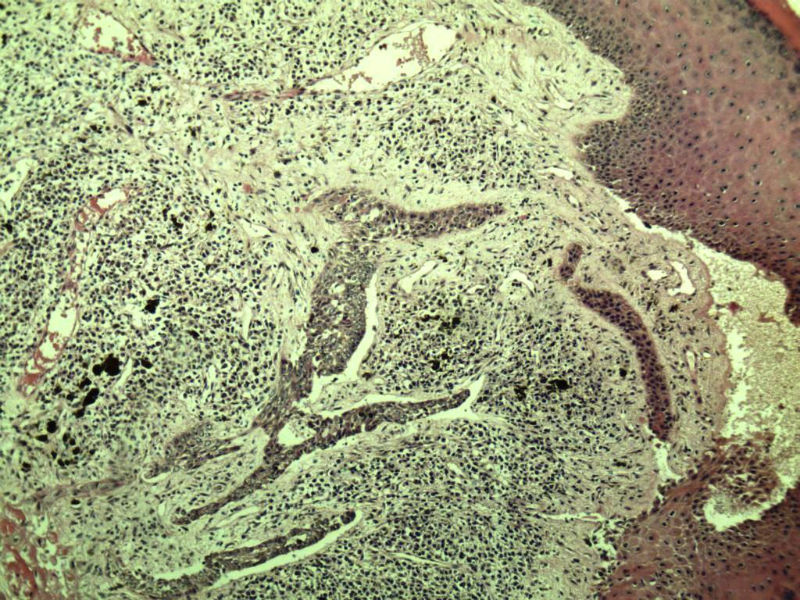

女 67岁 临床考虑面部色素痣 1*0.8 cm  请问各位老师 这是什么? 谢谢!面部包块图1

毛母/发细胞瘤鉴别基底细胞癌,可做CD10,CK7,CK20鉴别

考虑毛发上皮瘤,需除外基底细胞癌。

毛发上皮瘤,需与基底细胞癌鉴别

第一例:毛发上皮瘤

第一例:毛发上皮瘤,与基底细胞瘤区别明显。

第一例  毛发上皮瘤,和基底细胞癌鉴别一下

第一例考虑毛母细胞瘤,第二例考虑基底细胞癌。

毛母细胞瘤

第一例:毛母细胞瘤;第二例:基底细胞癌

第一例,毛发上皮瘤;第二例,基底细胞癌。

一毛发上皮瘤